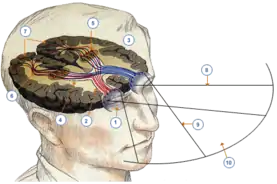

Зоровий нерв утворений аксонами гангліонарних клітин сітківки. Частина, яку можна побачити при огляді очного дна, називається диском зорового нерва (лат. discus nervi optici). Анатомічно утвір простягається від диска зорового нерва до перехрестя зорових нервів (лат. chiasma opticum), опісля віддає свої волокна зоровим шляхам (лат. tractus opticus). Кровопостачання складне, здійснюється в основному завдяки очній артерії (лат. arteria ophtalmica) та її гілкам. Більша частина крові відтікає у печеристу пазуху (лат. sinus cavernosus).

Приблизна довжина нерва в людини складає 5 см[8] (довжина може коливатися від 3,5 до 5,5 см[9]) і в ньому топографічно можна розрізнити чотири частини[8][10]:

Зорове перехрестя (лат. chiasma opticus) — це ділянка, у якій частина волокон зорового нерва переходить на протилежну сторону. Перехрещуються волокна, які прямують від носових частин сітківки (носові частини сітківки відповідають за скроневі поля зору). Таким чином, у зорових шляхах містяться волокна, які несуть інформацію про одне поле зору: лівий зоровий шлях прямує до лівої потиличної частки та містить волокна, які пов'язані з правим полем зору, а правий зоровий шлях прямує до правої потиличної частки і містить волокна, які пов'язані з лівим полем зору.[23][25]